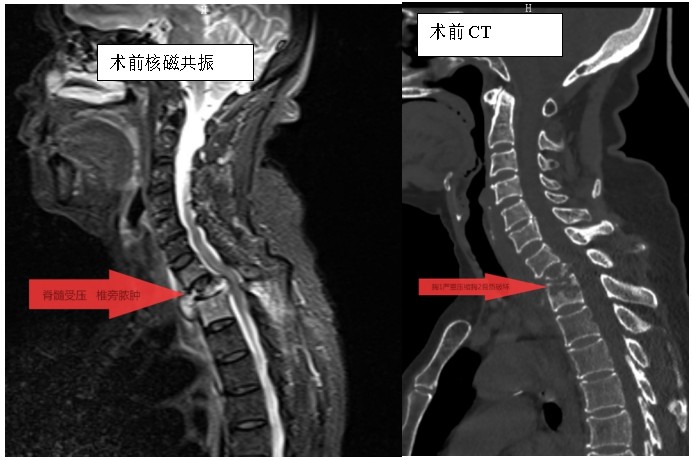

家住耒陽的70歲的李奶奶,因“頸胸背部疼痛不適伴雙上肢麻木6個月”,來到衡陽市中心醫(yī)院脊柱外科住院,住院當(dāng)天,患者頸胸椎核磁共振顯示:胸1、2椎體骨質(zhì)破壞,伴胸1、2椎旁軟組織腫脹、同層面椎管變窄,因脊髓受壓而導(dǎo)致頸胸背部疼痛。在錢軍博士帶領(lǐng)下,醫(yī)療團隊詳細(xì)予以完善相關(guān)檢查后,研究患者的臨床資料,考慮脊柱結(jié)核并椎旁膿腫的可能性大,由于患者胸1椎體病理性骨折并椎管狹窄,遂囑患者嚴(yán)格臥床休息,術(shù)前給予標(biāo)準(zhǔn)四聯(lián)抗結(jié)核藥物治療2周,以控制活動性結(jié)核感染,降低術(shù)中播散風(fēng)險,并嚴(yán)密監(jiān)測肝腎功能及血常規(guī)情況。